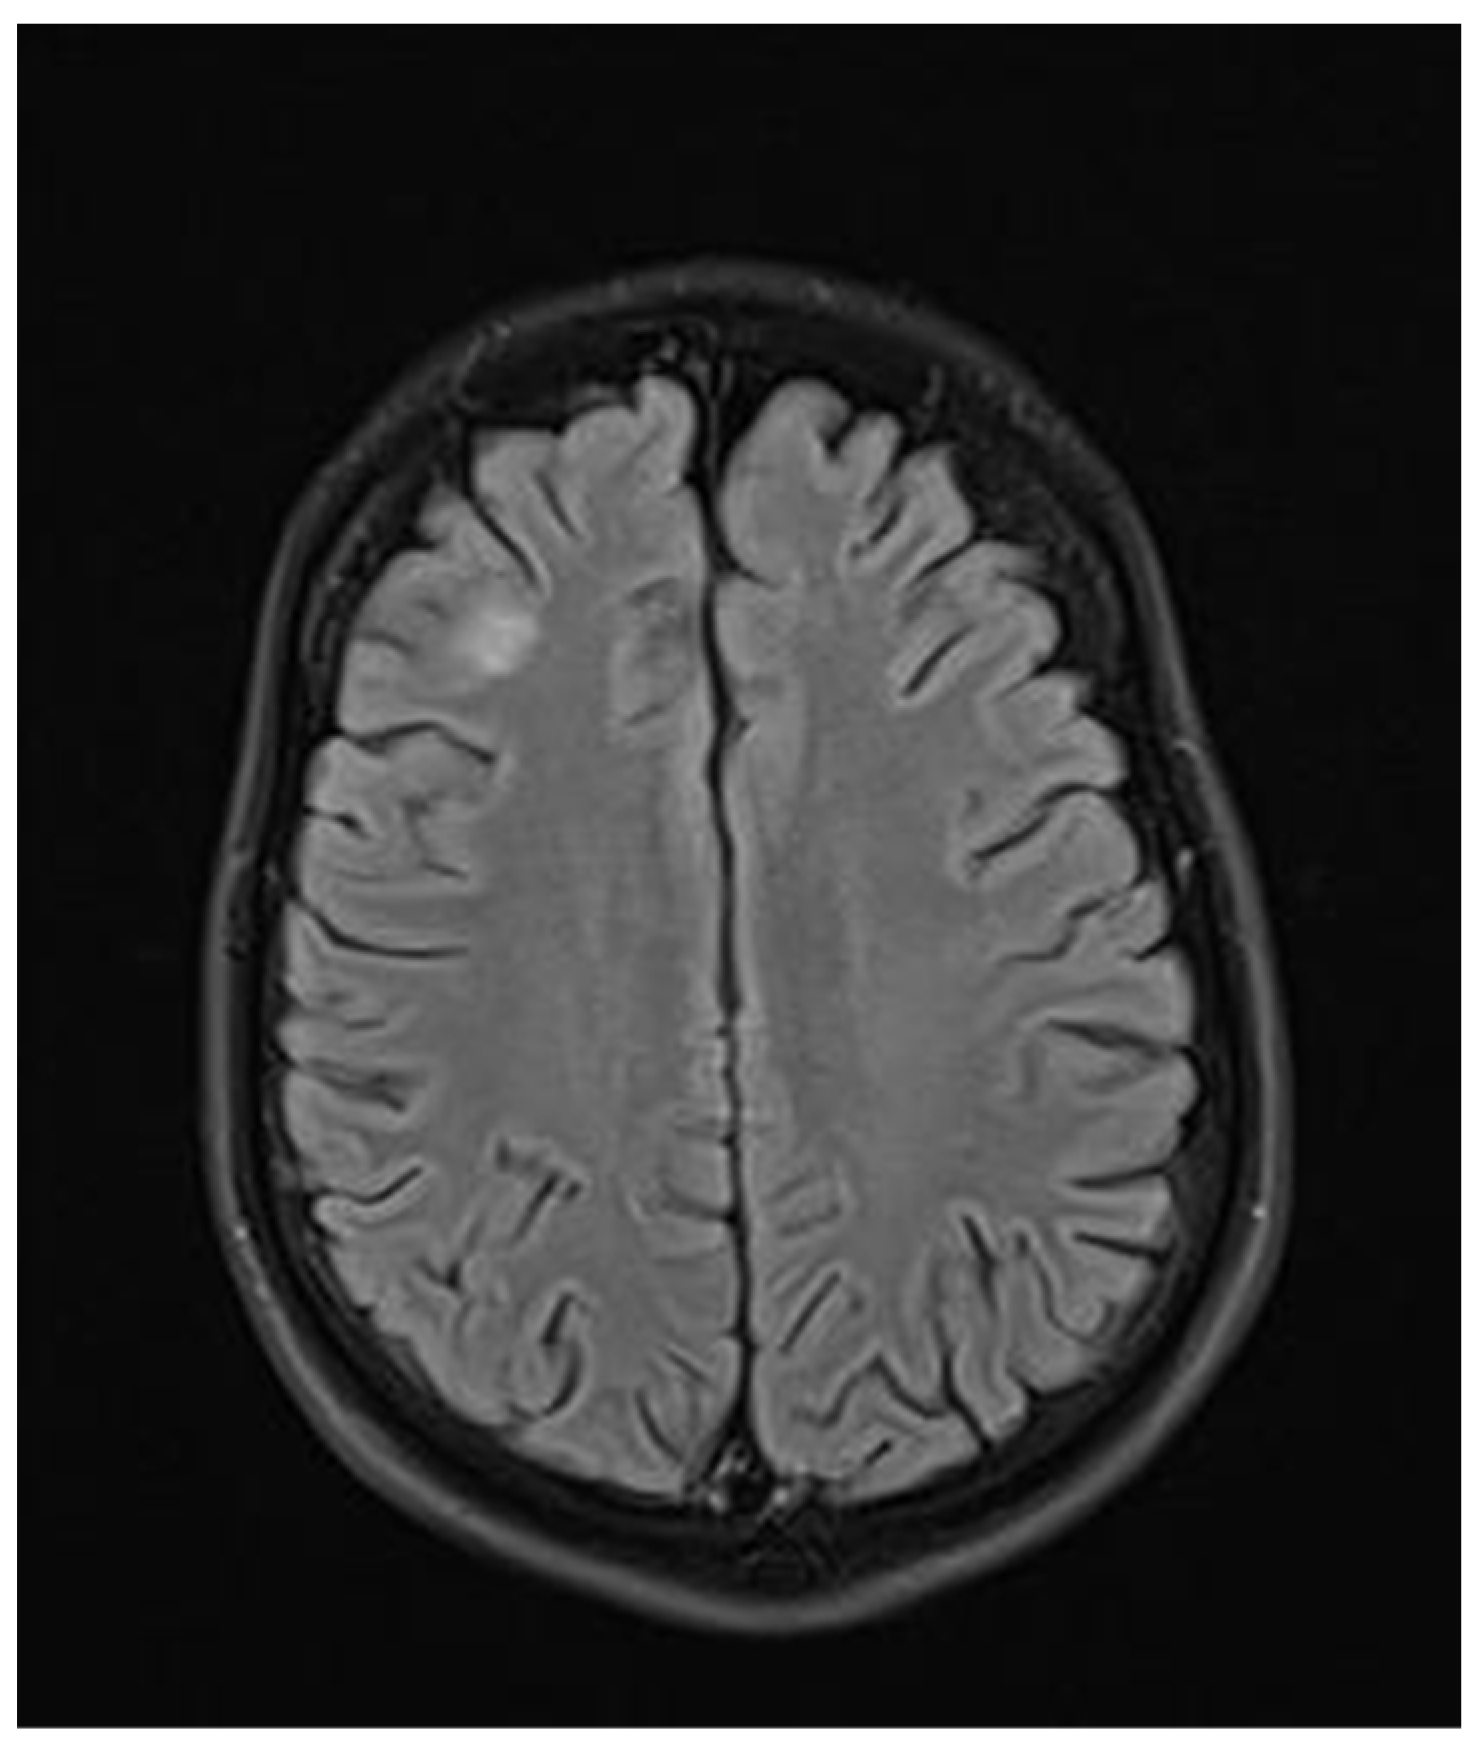

2. Case Report